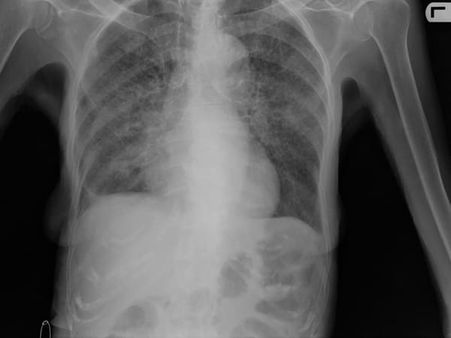

If your skin test result is positive, your doctor will conduct a chest X-ray or a CT scan. It will show the changes in the lungs caused by active TB. If the chest X-ray result is positive, your doctor will take samples of your sputum (mucus from your cough) to check for TB bacteria.